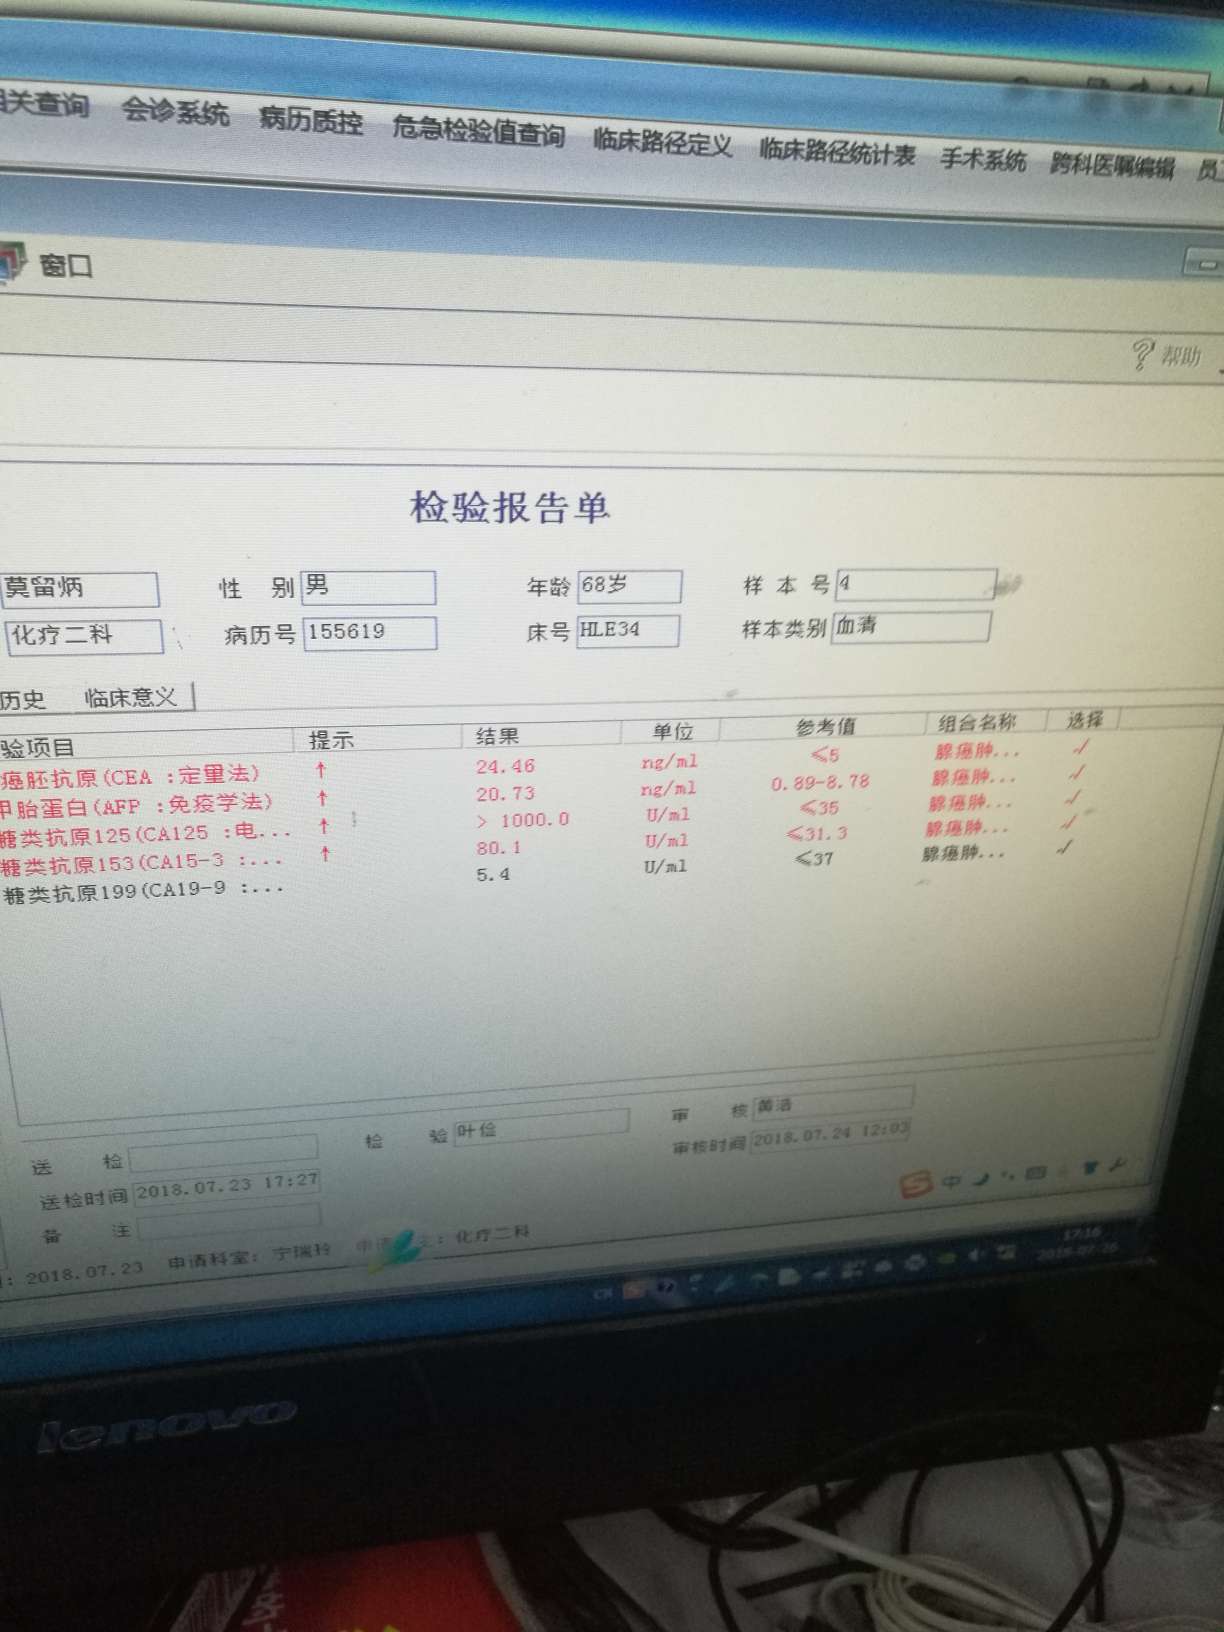

肝部阴影多了很多,骨转,肾上腺都有,同时疑似有脑转,肿瘤标志物数值也升幅很大

肝部阴影多了很多,骨转,肾上腺都有,同时疑似有脑转,肿瘤标志物数值也升幅很大